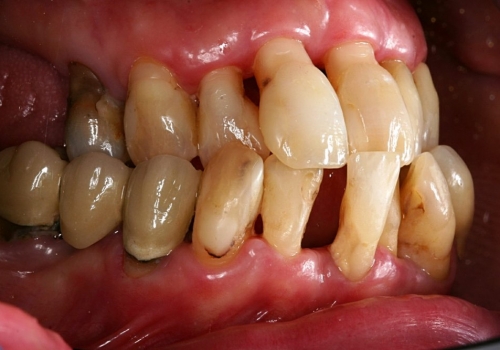

Çünki bu ciblər çox zaman pasiyent tərəfindən yetərincə təmizlənə bilmir. Bu isə həmin bölgəyə tədricən ərp və dolayısı ilə də bakteriya koloniyalarının toplanmasına səbəb olur. Bu proses yenidən yerli iltihabın ortaya çıxmasına səbəb olur. Tətbiq edilən cərrahi metodlar əsasən cibin yerləşdiyi diş bölgəsi, cibin eni, dərinliyi, konfiqurasiyası və s. xüsusiyyətlərə görə müəyyənləşdirilir. Bu zaman məqsəd mümkün olduqda həmin bölgədə bərpa prosedurunu həyata keçirmək, mümkün olmadıqda isə rezektiv müalicənin tətbiqi ilə həmin bölgəyə ərp toplanma ehtimalını azaltmaq və gigiyenik prosedurların icrasını pasiyent üçün rahatlaşdırmaqdır.

Rezektiv prosedurlar zamanı müəyyən miqdarda yumuşaq toxuma (diş əti), sərt toxuma (sümük) və ya kombinə olunmuş şəkildə (həm sümük, həm də yumuşaq toxuma) rezeksiya həyata keçirilir. Prosedur yerli ağrısızlaşdırma altında aparılır. Əməliyyatdan sonrakı dövrdə fərdi qulluq və gigiyena qaydalarının mötəxəssis tərəfindən izahı və müvafiq instruksiyanın verilməsi olduqca önəmlidir.